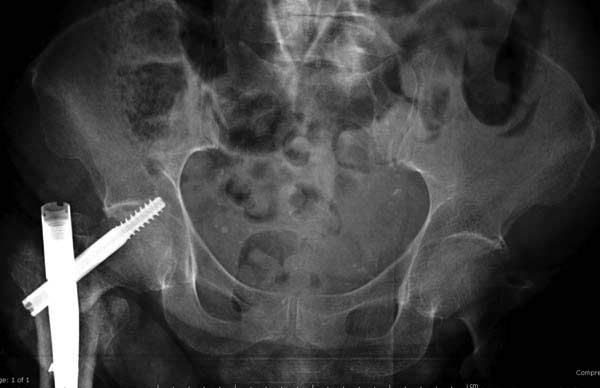

Третья операция-продолжения усилии "синьорами пэрами" по разрушению нормальной анатомии. Крест на головку! По видимому возраст позволяет биполярную конструкции, и при дефекте  calcar пошли на обычный цементный. Ягодичные мышцы потеряли связь с вертелом, т.е. отсутствует верхний удержатель, и результат “a Big Screw Up!” Снимки вызывают головокружение!

Если хирурги не устали от своих “творчеств”, тогда можно ре-оперировать с calcar replacement stem, и собрать остаток ягодичных мышц. Глубина и отстутствие артроза позволяет применить любой, биполярный или тотальный, хотя принять решение можно после ревизии ацетабулума.